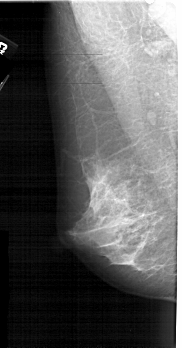

A_1907_1.LEFT_MLO

LEFT_MLO LINES 5206 PIXELS_PER_LINE 2716 BITS_PER_PIXEL 12 RESOLUTION 43.5 NON_OVERLAY